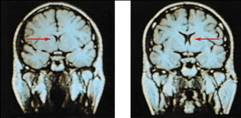

MRI Scan

74

Visual Function

• Functional MRI scan shows the visual cortex activates as the subject looks at faces.

85

Auditory Function

• Functional MRI scan shows the auditory cortex is activated in patients who hallucinate (hear voices).